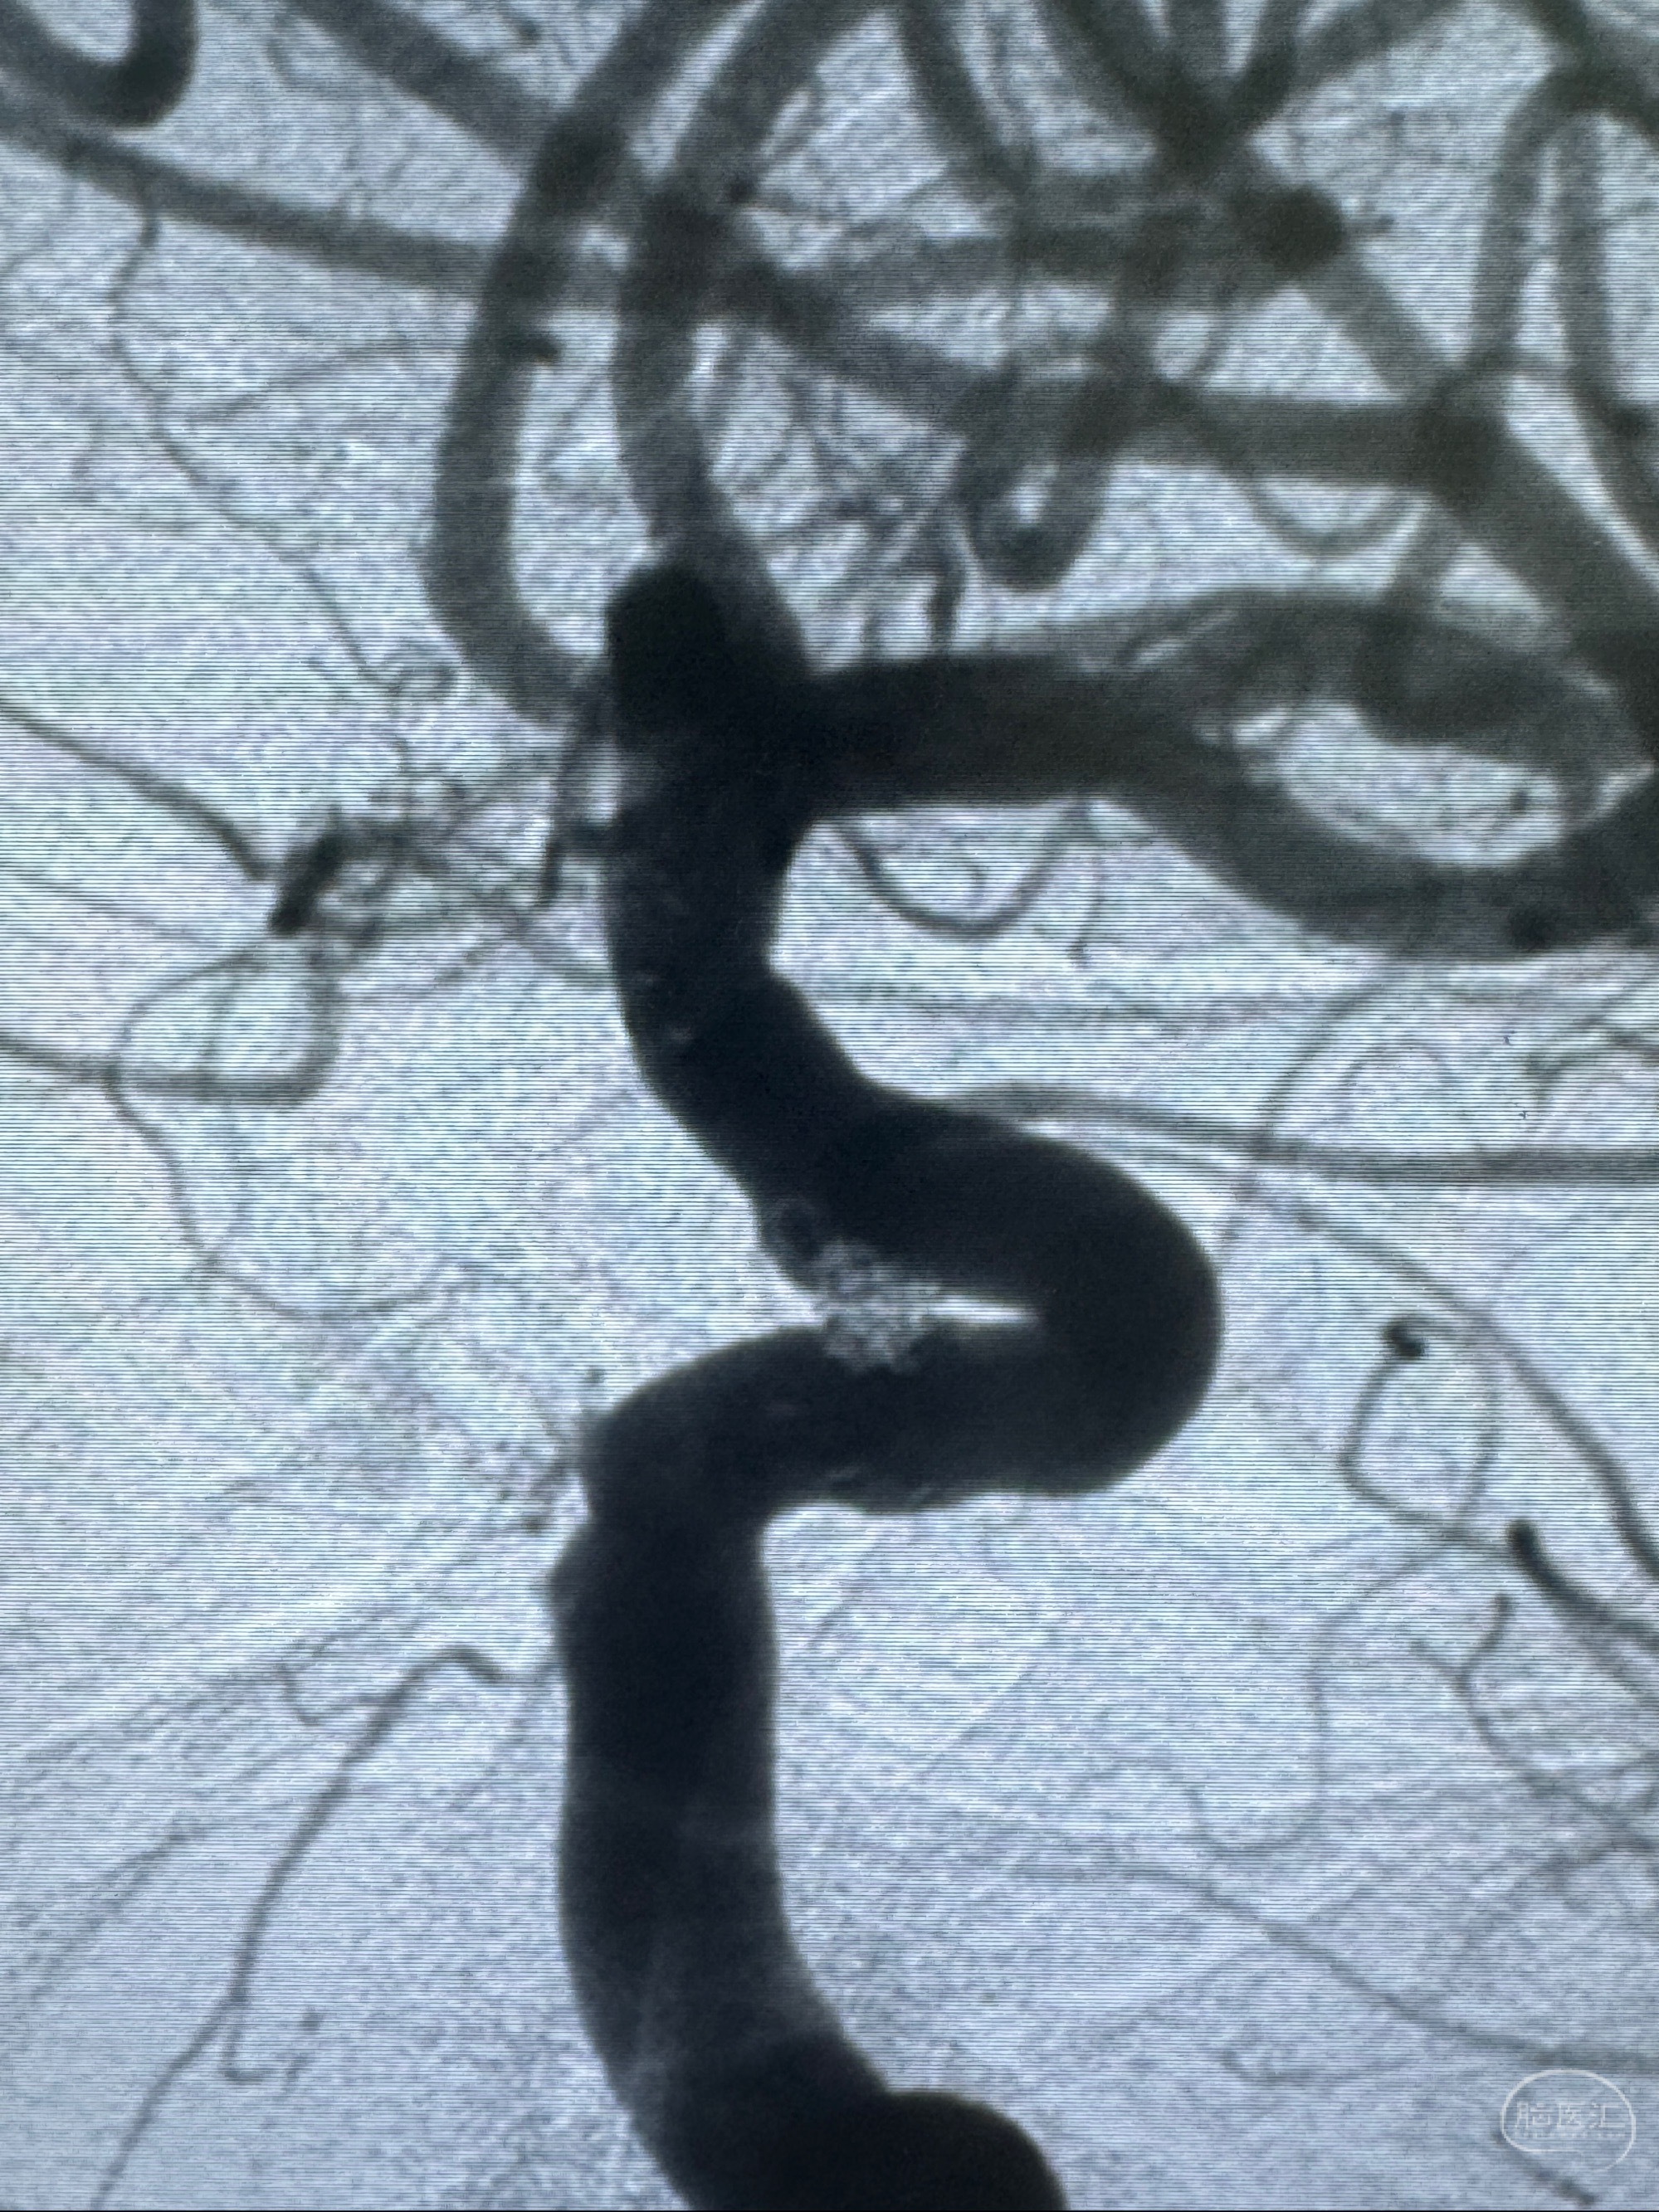

2023-11-13DSA:左侧颈内动脉眼动脉后壁动脉瘤

2023-11-29全麻下行NeuroformEZ4.5-20mm支架辅助栓塞